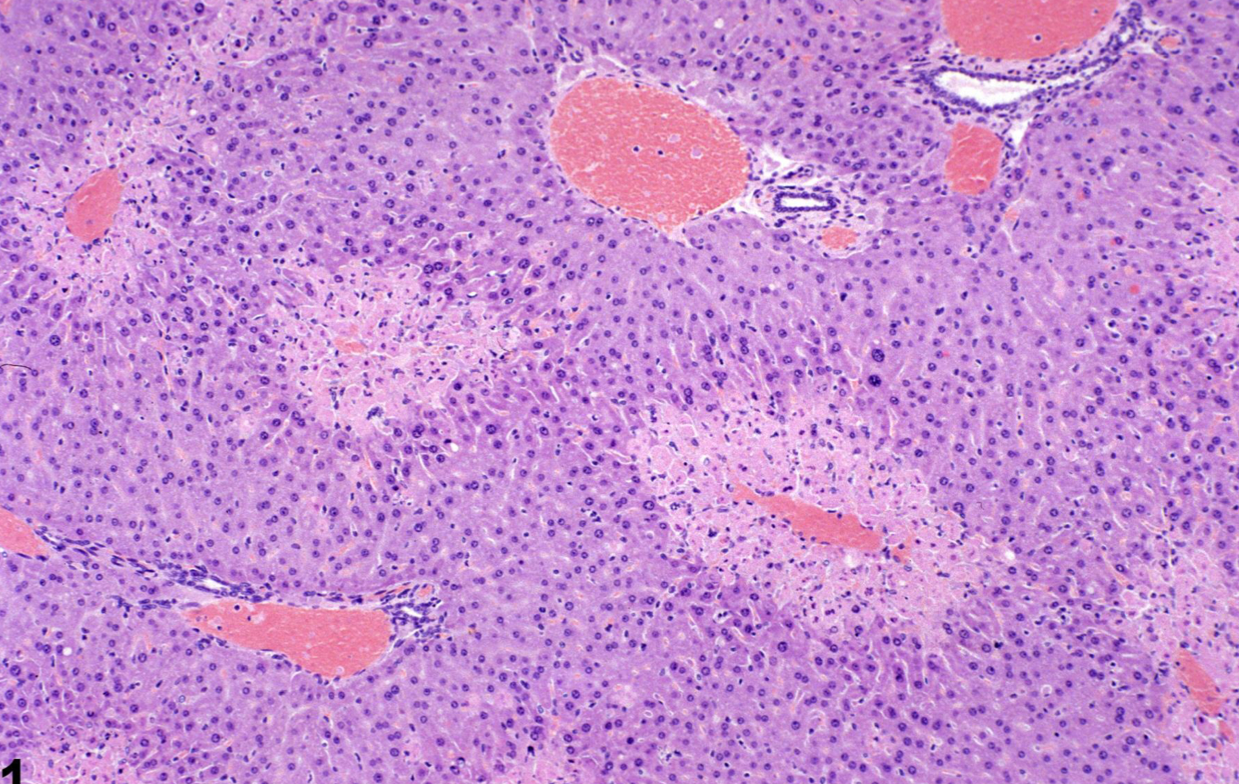

Migration of Fascioloides magna in an Ox liver is an example of what pattern of necrosis?

Focal/Multifocal

*This pattern can also be seen with infection (Salmonellosis) and trauma, and is accompanied by inflammation (hepatitis)